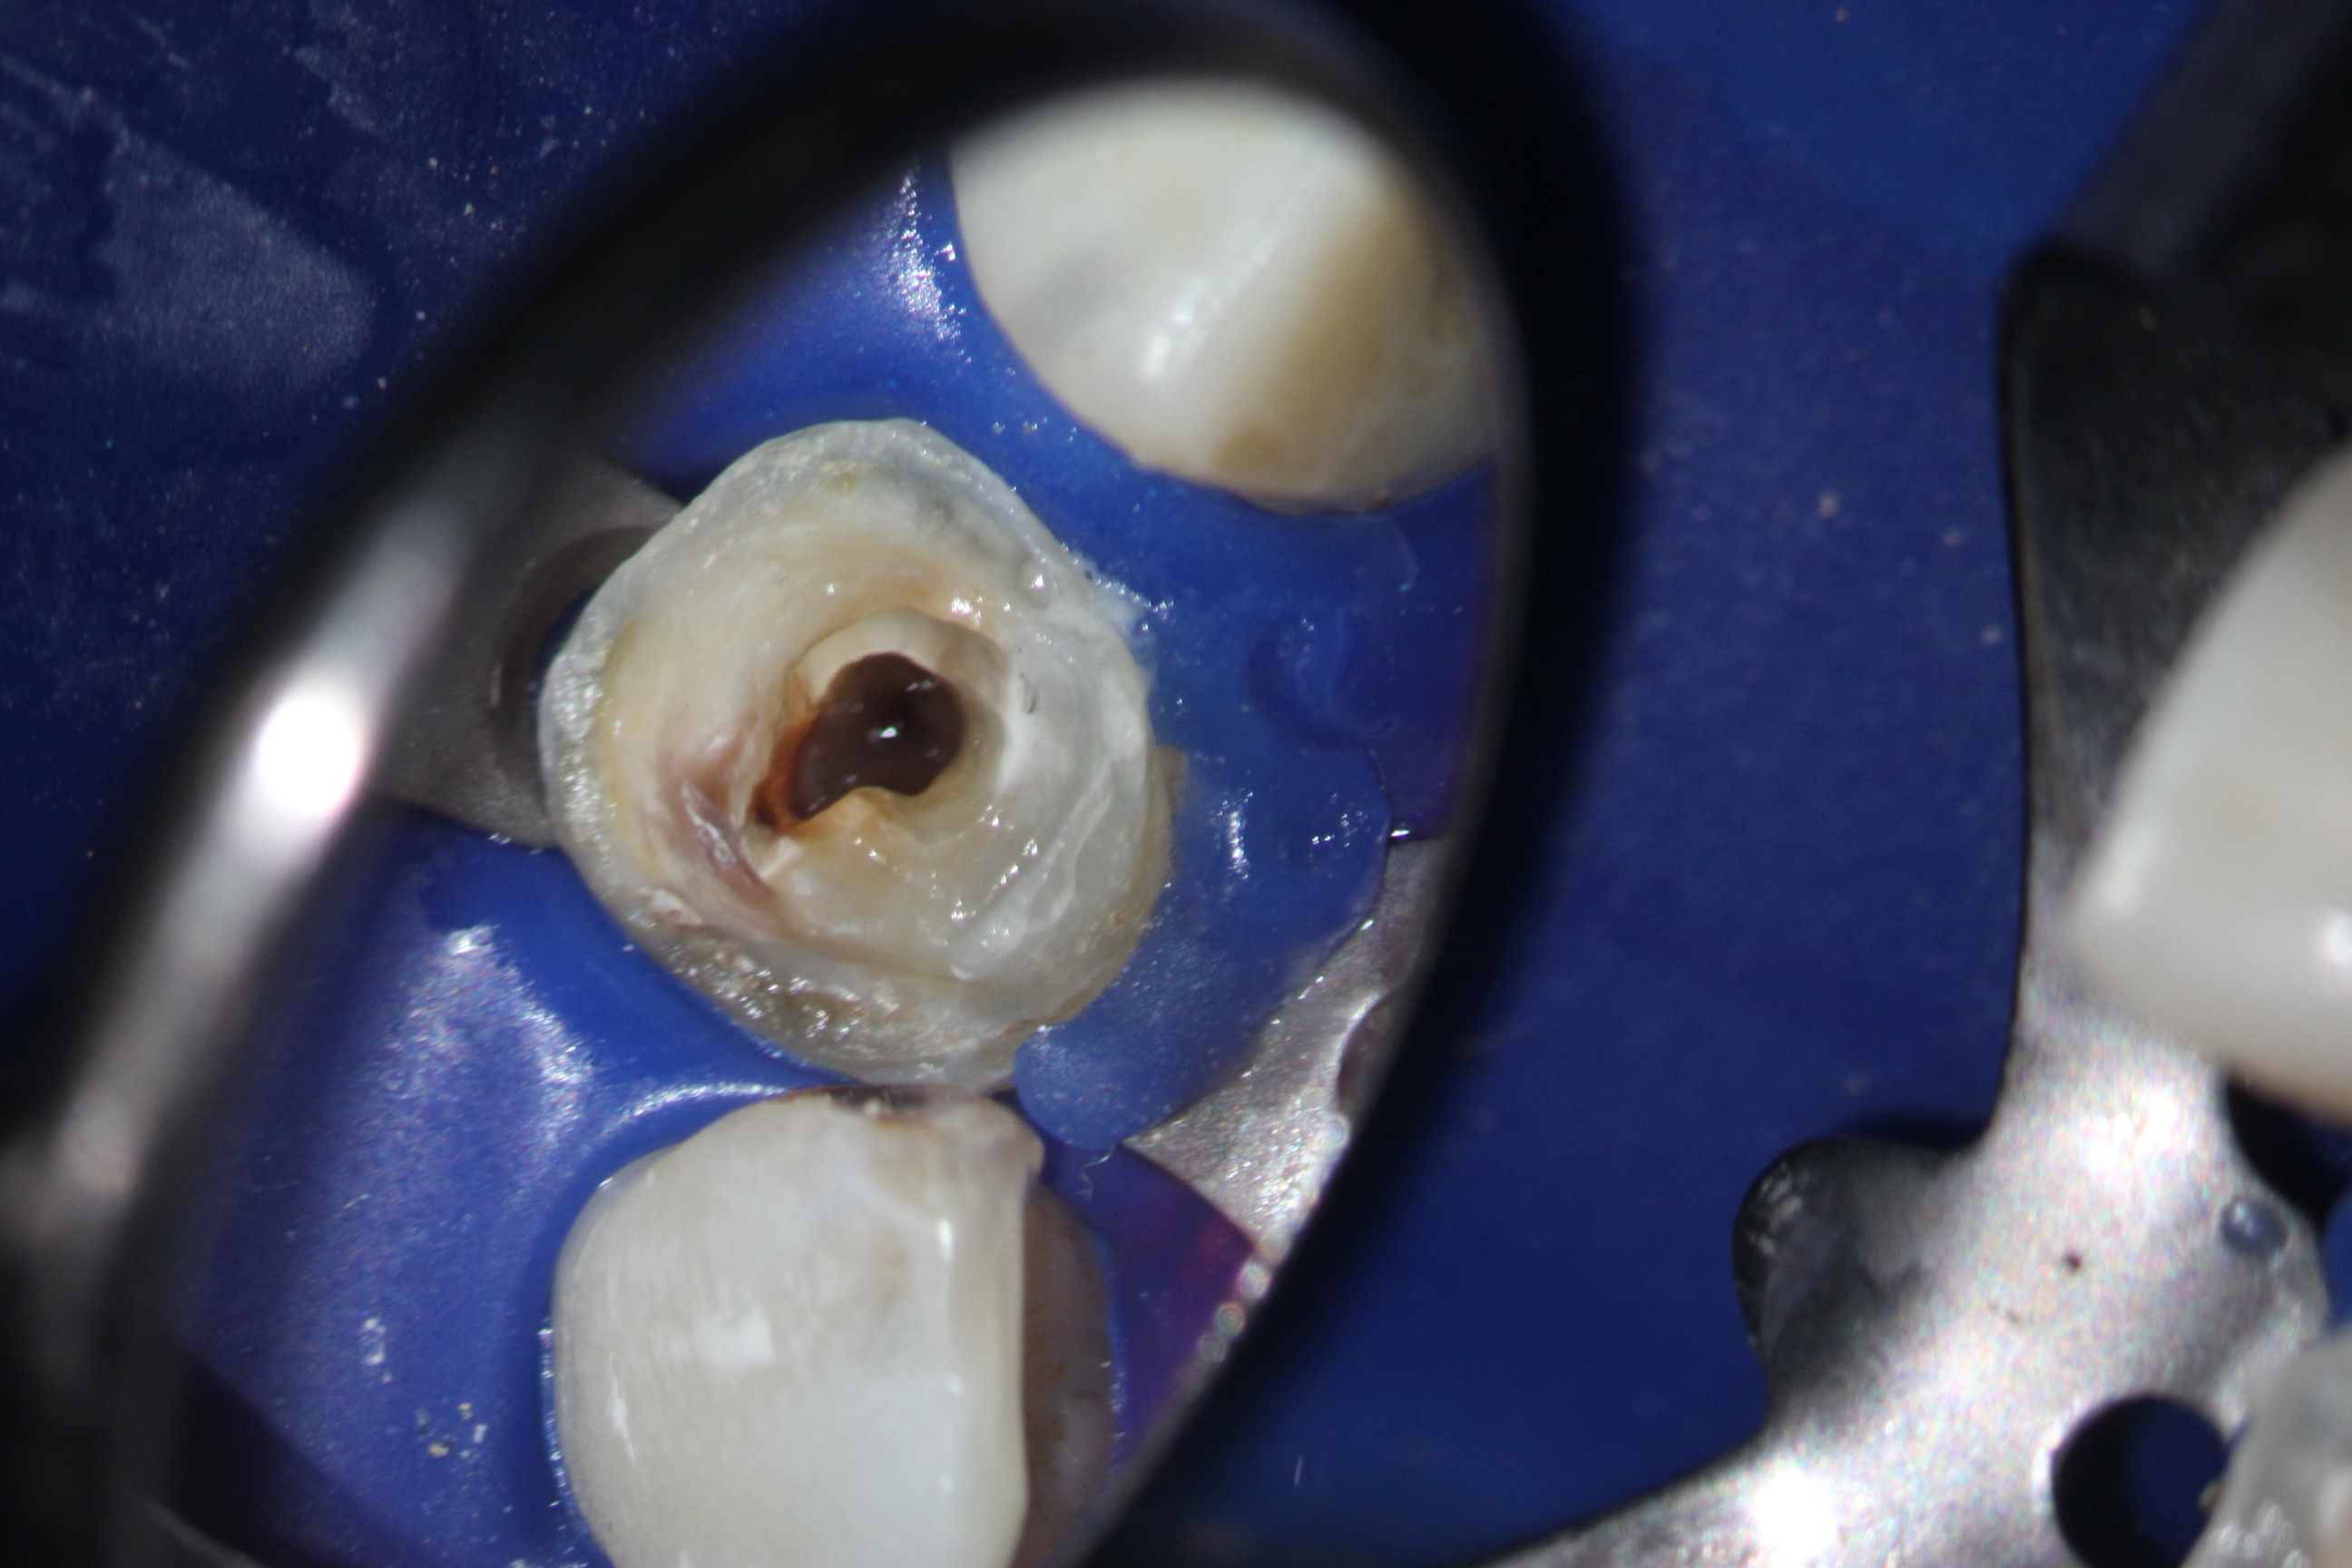

und wieder ein Recall

Nach Instrumententfernung